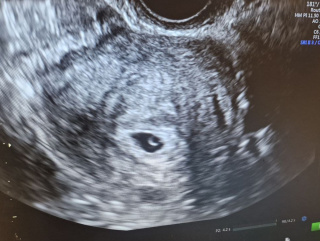

Під час гінекологічного огляду та ультразвукового дослідження органів малого таза було виявлено міому матки.

Порожнину матки заповнював великий субмукозний міоматозний вузол діаметром близько 5 см. Саме він був основною причиною кровотеч та розвитку важкої анемії.